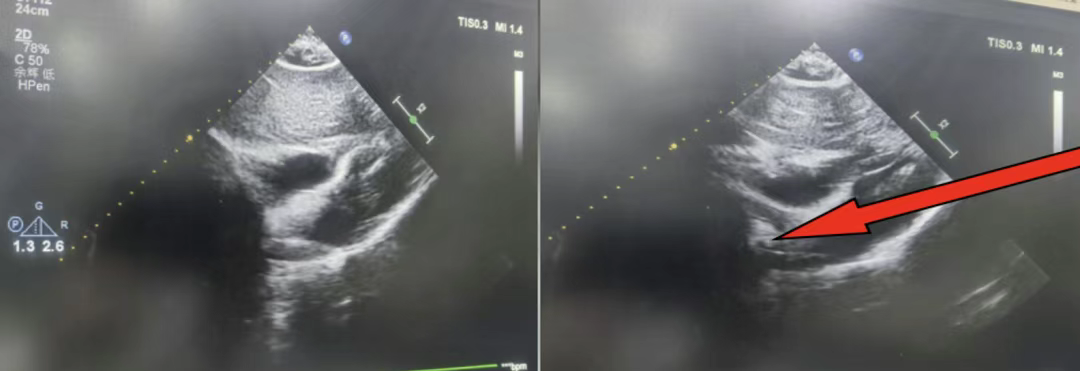

1 个月后,郑女士再次入院,任主任团队为其顺利完成房间隔封堵术。两次手术均圆满成功,目前患者恢复良好,已顺利康复出院。